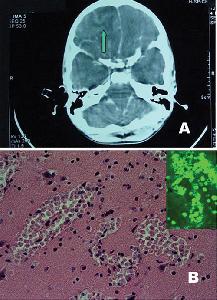

Hình ảnh ký sinh trùng amip Naegleria fowleri tấn công và "ăn não" - Ảnh: CDC

Ký sinh trùng này chui vào cơ thể bằng đường mũi. Khi xâm nhập cơ thể người, amip Naegleria fowleri sinh sôi rất nhanh, sau đó di chuyển lên não. Tại não, loại amip này hầu như không tiếp tục di chuyển mà tồn tại, ký sinh ở đó và chủ yếu sống bằng nguồn dinh dưỡng nhờ ăn các tế bào não.

Bị nhiễm amip Naegleria fowleri, bệnh nhân sẽ bị viêm màng não.

Triệu chứng lâm sàng chính của bệnh nhân khi bị nhiễm loại amip Naegleria fowleri thường là sốt nhẹ, đau đầu, cứng cổ. Vào thời kỳ cuối, khi não người bệnh đã bị amip Naegleria fowleri phá hủy nghiêm trọng, bệnh nhân có triệu chứng tâm thần, thay đổi hành vi, có ảo giác rồi dẫn đến tử vong.